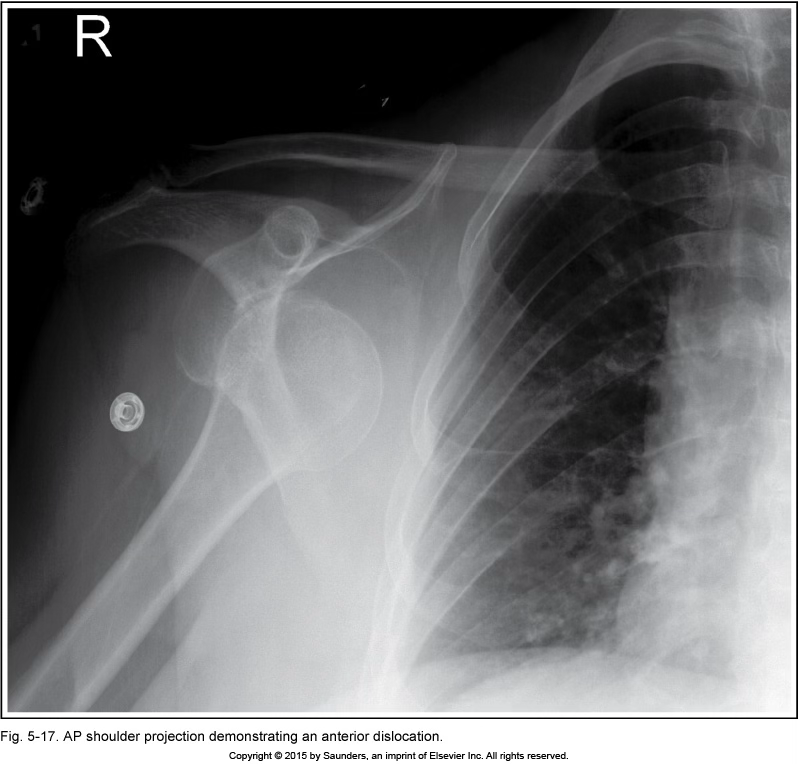

AP shoulder (dislocation)

MCP tilt anteriorly (superior angle above clavicles)

anterior dislocation

MCP tilt posteriorly (clavicle above superior angle)